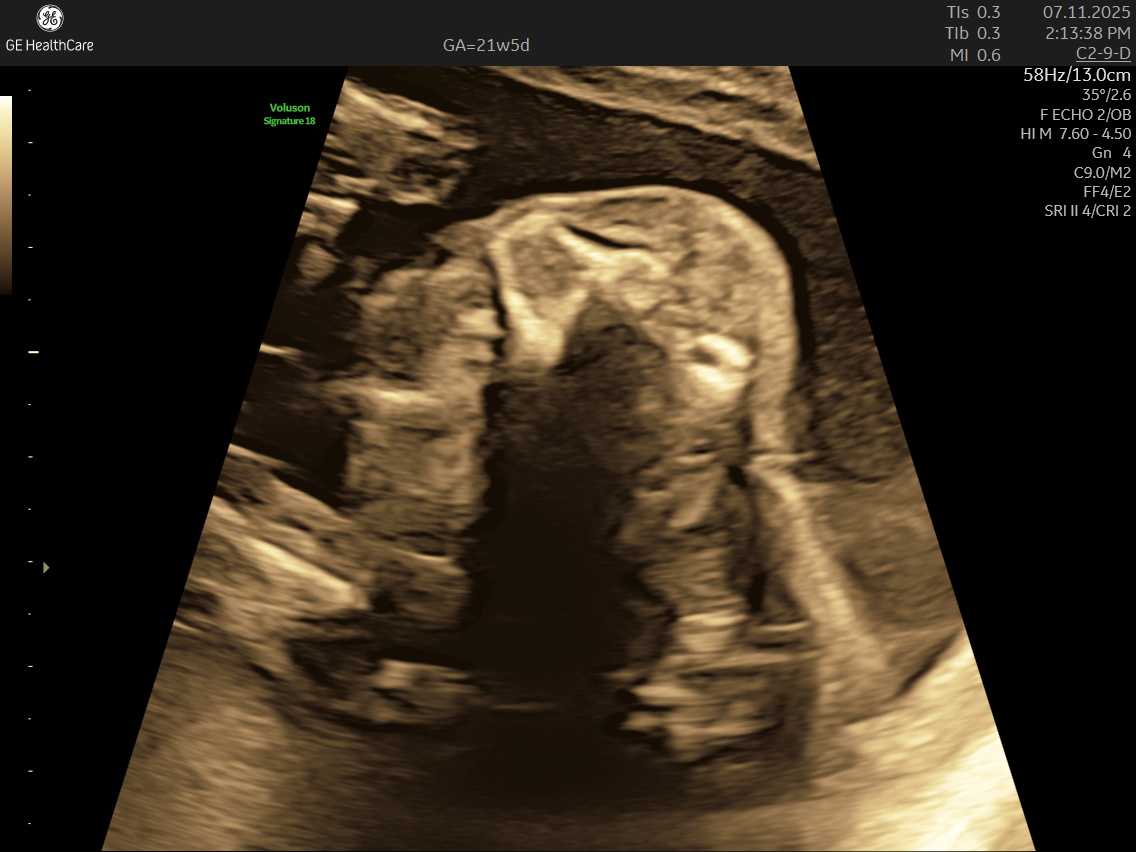

IMAGE GALLERY

If you’re expecting a baby, the Detailed Anatomy Scan —also known as the Fetal Anomaly Scan — is one of the most important checks you’ll have during pregnancy. Usually done between 18 and 22 weeks, this ultrasound is performed by highly trained fetal medicine specialists at NESA Institute of Fetal Medicine. The scan provides a close-up look at your baby’s overall development and helps to make sure everything is progressing as it should.

During this scan, the MFM specialist carries out a detailed examination of your baby’s body, checking their vital organs, spine, head, heart, limbs, and more. The aim is to confirm that your baby’s growth is on track and can identify various structural abnormalities and potential complications early, so that appropriate steps can be taken early.